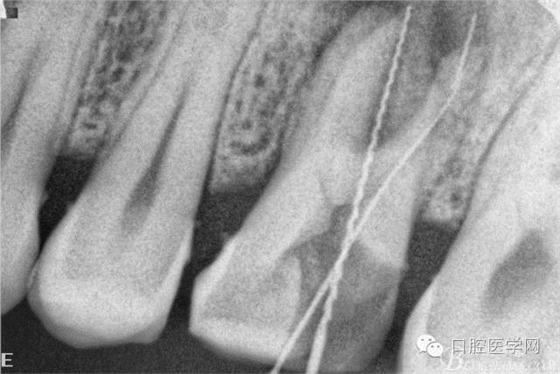

擴(kuò)根片(可惜遠(yuǎn)頰根有一斷針)